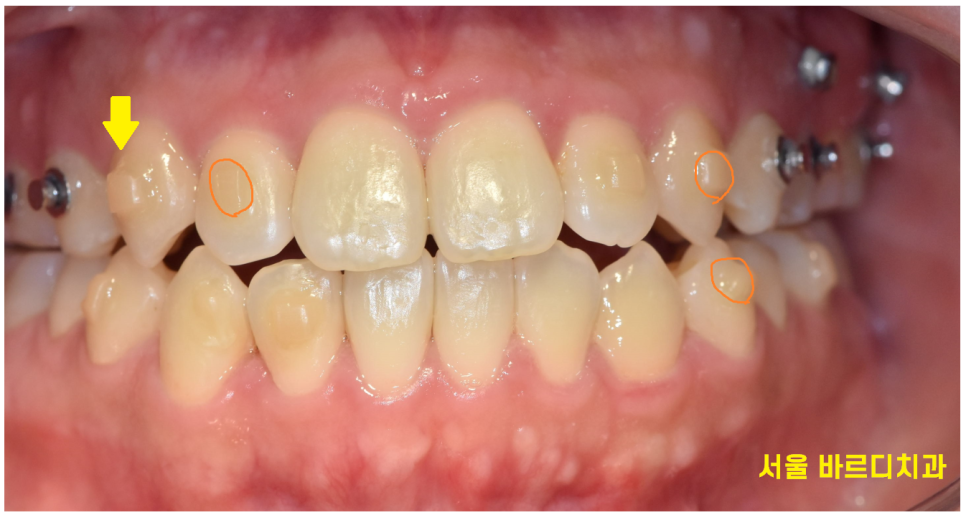

교정 효과를 극대화하기 위해 미니스크류를 심기도 하고

치아에 어태치먼트를 붙이기도 하거든요~~

여기서 치아교정 상식

"어태치먼트란???"

사진을 보면 치아의 겉면에 무언가 붙어있죠~?

치아 이동을 효과적으로 돕기위해 설치한다 보시면 됩니다.

아무리 치아 색상에 맞춰 붙여드려도,,

돌출감이 있기 때문에 티가 납니다.

교정하는 티가 하나도 안나려면 설측교정으로 진행하셔야한답니다...